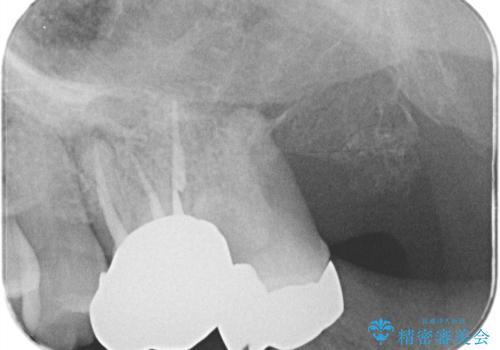

【根管治療】ズーンと痛い歯の治療。

- 奥歯付近がジーンと痛いことを主訴に来院されました。

左上7番の歯は、歯髄検査にて反応を示し、歯周ポケットはありませんでした。

親知らず抜歯を行い、痛みの変化や歯根吸収の有無を確認したのち、抜髄処置を行っています。

症状改善し、遠心の骨の回復も認めます。

バイオセラミックシーラーを使用して根管充填を行っています。